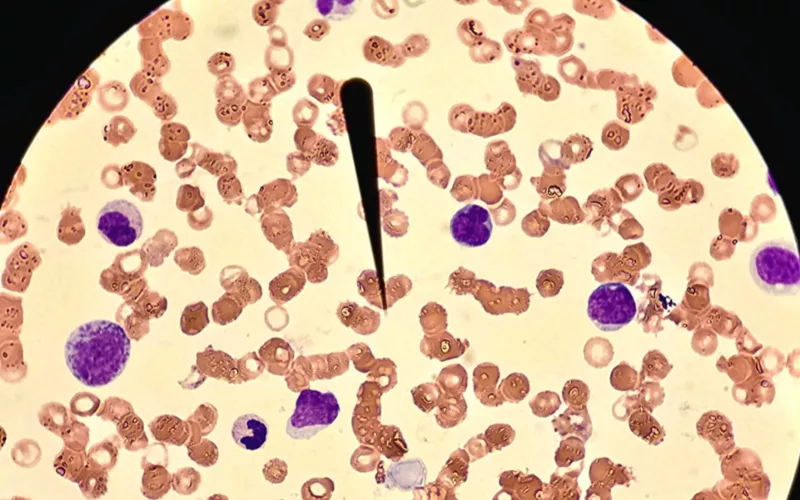

Para estas pruebas se emplean equipos automatizados de alta tecnología, que

permiten una detección y tratamiento oportunos, de diversas enfermedades.

El laboratorio clínico opera bajo altos estándares de calidad y es evaluado

mensualmente a través del programa de control de calidad externo “Pacal” en

cuanto a bacteriología, uroanálisis, hematología, coagulación, parasitología,

inmunología y química clínica.